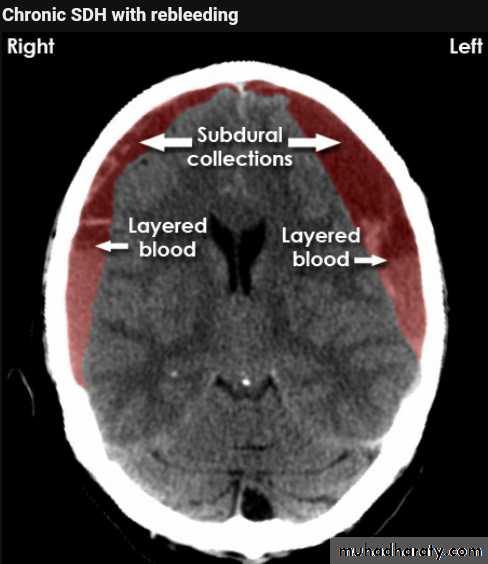

Acute SDH

CT findingCrescent shape or oval shape of hyper density area their inner medial margin is irregular shaggy

Associated with edema which cause shifting of the midline .

The source of bleeding hematoma is venous , not associated with # , but occur as a result of disruption of subdural vein , more commonly to occur in the old age group , due to brain concussion , ( brain atrophied wide SAS ) & in the pediatric age group the SAS &cistern are wide also .